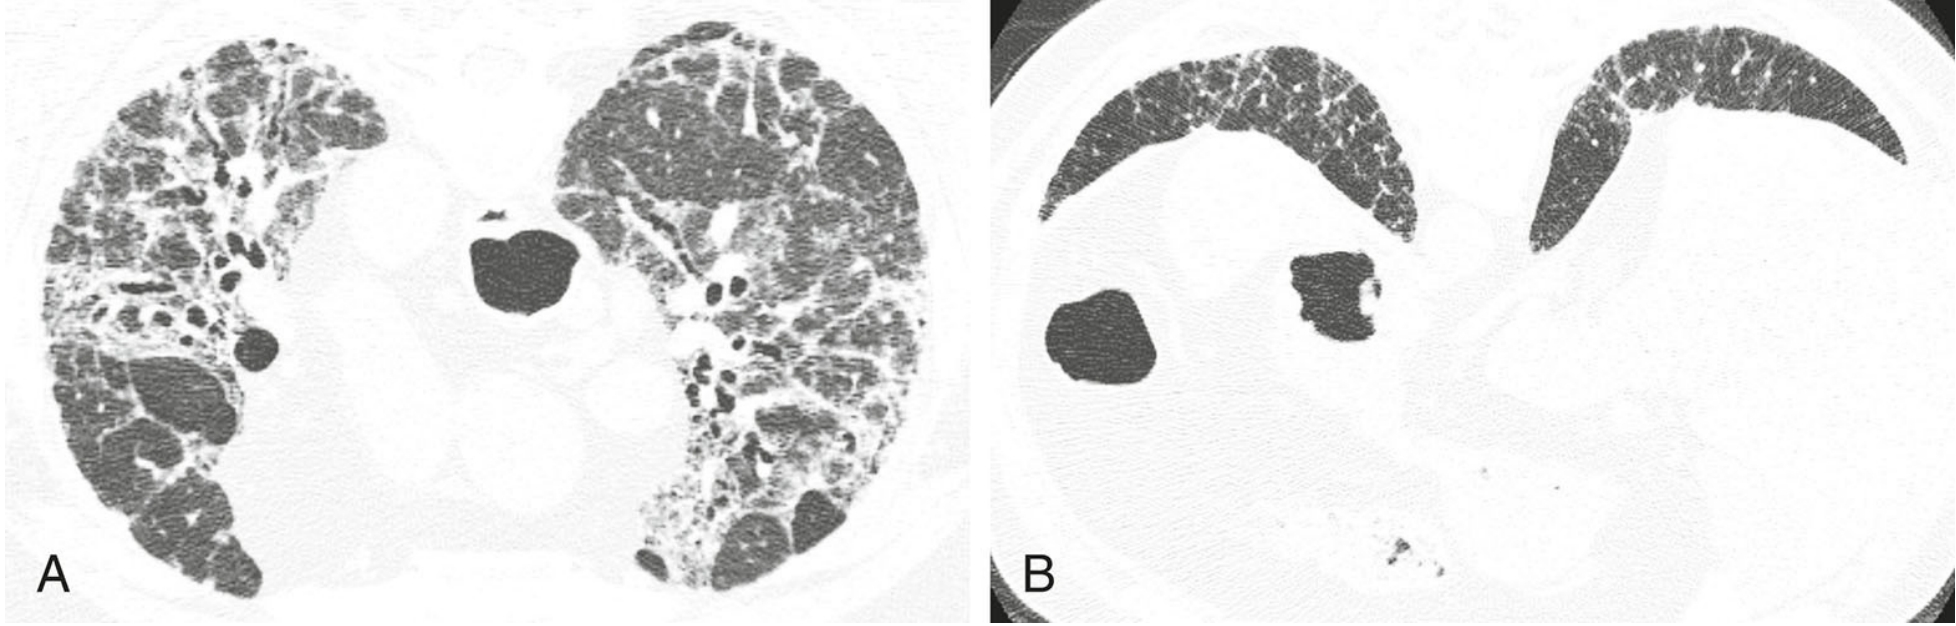

当根据HRCT表现而考虑诊断UIP模式时,鉴别诊断包括特发性肺纤维化、结缔组织病、石棉沉着病和药物中毒。这些疾病在HRCT上通常难以区分, 病理上可能也很难鉴别。

7331218b6857cead2350daf293806044.png

高置信度诊断为普通型间质性肺炎(UIP)的鉴别诊断。

4例UIP的HRCT表现;继发于特发性肺纤维化(A)、结缔组织病(B)、石棉沉着病(C)和药物中毒(D)的UIP, 均可见胸膜下及肺基底分布为主的纤维化伴蜂窝征。当表现为UIP模式时,上述疾病在HRCT上通常无法鉴别。